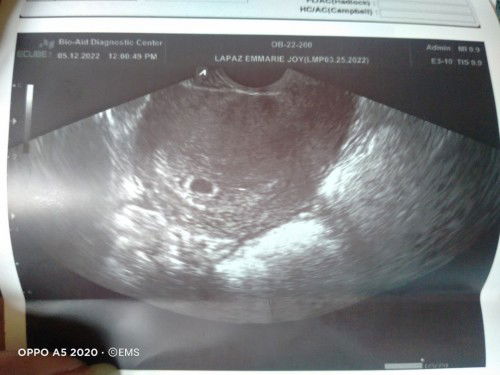

Praning about Blighted Ovum Case.

Hi mga mamsh, if you can remember me. Ako yung napapraning about Blighted Ovum Cases. dahil sa mga articles na nababasa ko dito sa App nung mga unang weeks ko palang na preggy. I had my 1st utz nung May 12, 4weeks & 4days palang akong preggy and Ges. Sac palang ang nakita, No yolk and No Embryo. then June 12 sana next utz ko para makita if nagdevelope si Baby but since ang gulo ng sched sa Hospital na una kong pinagpacheck up-an, lumipat ako ng clinic hehe. and nagpa utz ako kahapon June 7. based sa 2nd pic. buo na si baby, and may heartbeat na din 🥰 180 bpm per minute and 8weeks & 4days na rin sya based sa laki nya, ang sigla sigla kasi nagpakitang gilas pa sa OB pati sakin kasi naglililikot. 😅 So ayun Skl po, kaya sa mga kagaya kong napapraning kakaisip dahil ges. sac lang ang nakikita at wala pang baby na nakita, Inom lang po kayo Foralivit, basta may folic acid, malaking help sa pagdedevelope ni baby. Umiinom din ako ng Anmum choco kahit lately di talaga ko makapagbedrest dahil madami akong kelangan asikasuhin, kapit pa rin si baby 😍 wag tayo mapraning mga mamsh ha? kasi nararamdaman din ni baby yun hehe. yun lang, and have a safe pregnancy sating lahat 💖❤️#1stimemom #pregnancy